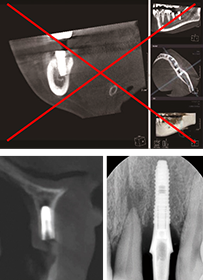

- 3D 컴퓨터 모의수술로 치료계획 후 식립합니다

- 시술 전 3D 컴퓨터 모의수술을 통해 환자의 골조직과 신경위치 등을 파악하여 최상의 치료계획을 수립하고 개별맞춤

수술유도장치를 사용하므로 신경손상 및 잘못된 임플란트 시술의 위험이 적습니다. - 무절개 시술로 빠른 회복이 가능합니다